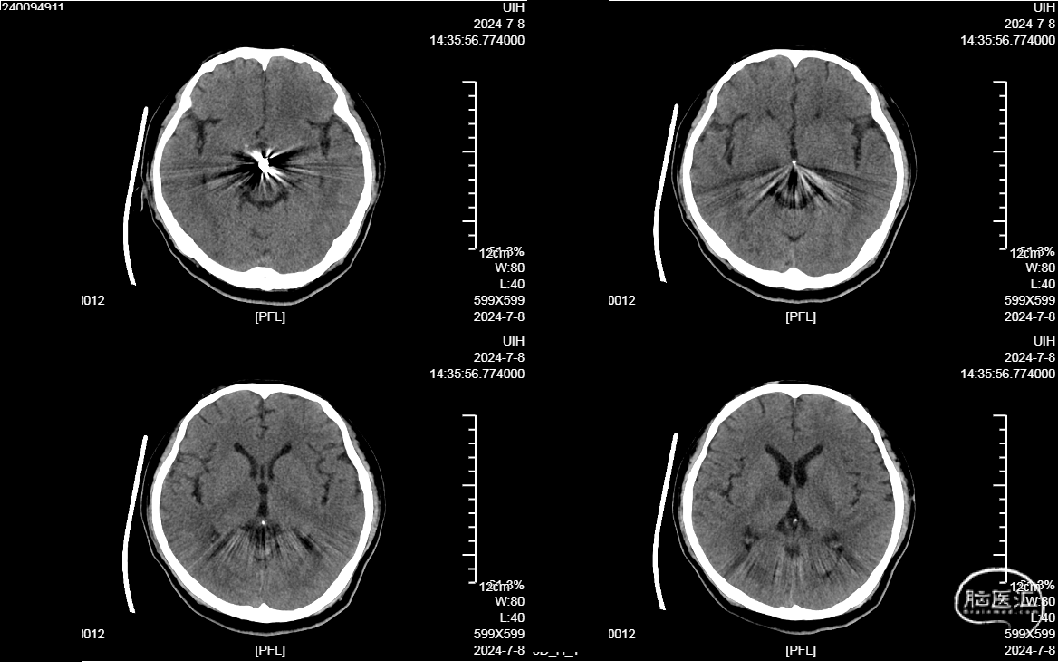

外院CTA示:

1.右侧大脑脚-右侧丘脑急性脑梗死。

2.右侧大脑后动脉P1、2段显影差,P3及其以下未见显影;建议结合临床。

3.结合CTA,符合右侧颈内动脉C7、基底动脉末端动脉瘤。

4.鼻窦炎。

右侧中脑-丘脑可见新发脑梗塞:

颅内外血管未见明显狭窄。

CT(CTA)检查提示:右颈内动脉C7段大小约3.6×3.8×3.6mm及基底动脉远端动脉瘤形成大小约9.7×7.6×9.3mm。